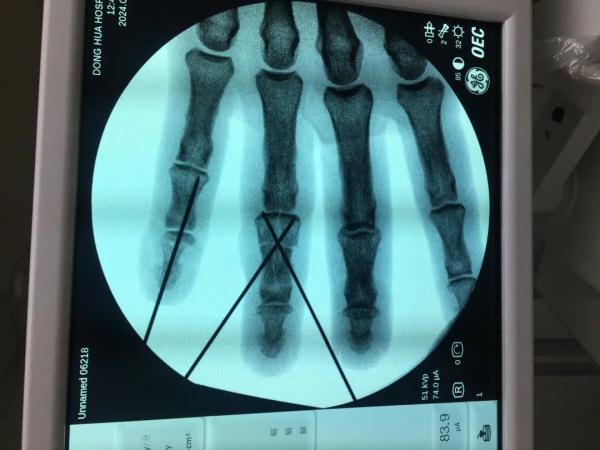

接诊的医生见其左手中环指近指间关节皮肤软组织不规则创口,创缘不齐,环指中末节严重肿胀,中节可及骨擦感,并经X线等专业检查,以左手环指中节开放指骨骨折伴神经血管肌腱损伤等创伤将其收治入院,并与助手孙晓红、尹齐齐立即对其施行手术。

环指掌侧切开,创口内可见中节指骨粉碎骨折、缺损,屈指深肌腱部分断裂,环指双侧指神经及指动脉撕脱断裂、缺损,双侧指动脉栓塞、血栓形成。

根据其环指损伤的具体情况,医生于环指掌侧再作辅助切口,对粉碎骨折的左手环指中节指骨复位后固定,用骨修复材料进行植骨修复,并缝合修复部分断裂的屈指深肌腱。

见双侧指动脉、指神经缺损,血管、神经张力较大不能直接缝合,医生又于前臂掌侧取同等管径皮下静脉1条,分成两段后血管倒置后予以移植。同时于前臂掌侧取皮下神经1条,分成两段后予以移植。